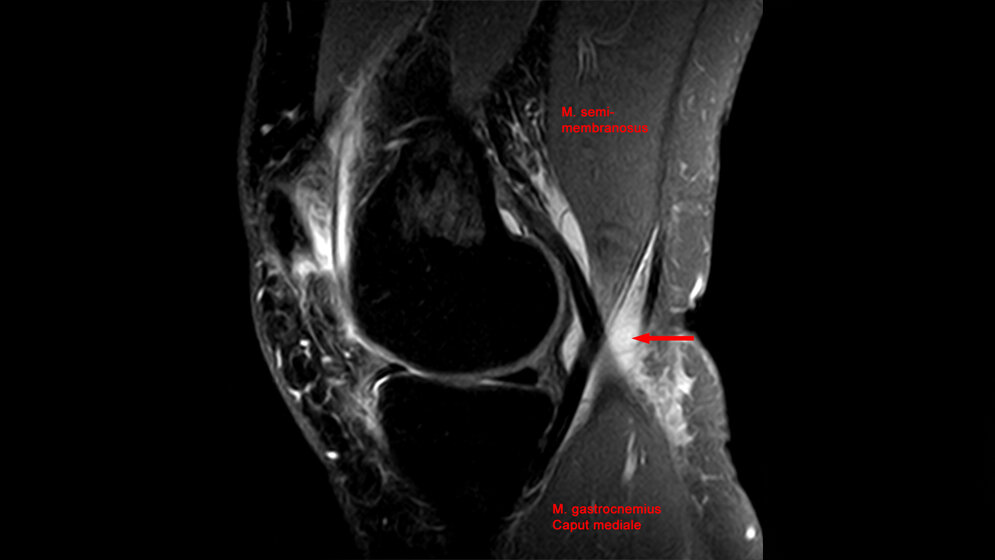

Eine Baker-Zyste bezeichnet eine Zyste im Bereich der Kniekehle, die häufig bei Arthrosen oder auch weiteren Erkrankungen im Knie wie einer Verletzung des Meniskus auftritt. Neben den Beschwerden der primären Erkrankung, verursacht die Zyste bei vielen Patienten zusätzlich ein permanentes Druckgefühl. Häufig führt sie auch zu Funktionseinschränkungen, da das Knie nicht mehr störungsfrei abgewinkelt werden kann. Die Baker-Zyste gilt als Begleiterscheinung, weswegen bislang ursächlich nur die entsprechende Grunderkrankung behandelt werden kann. Wenn die Zyste anhaltend Beschwerden verursacht, kann sie aber operativ entfernt werden. Dr. Matthias Hautmann aus der Klinik und Poliklinik für Strahlentherapie des UKR hat nun bei der strahlentherapeutischen Behandlung von Patienten mit Knie-Arthrose entdeckt, dass sich diese Therapieform auch günstig auf die Baker-Zyste auswirkt. Diese, in einer prospektiven Studie veröffentlichten Ergebnisse, wurden auf der Jahrestagung der Deutschen Gesellschaft für Radioonkologie mit dem Günther-von-Pannewitz-Preis ausgezeichnet.

Baker-Zysten entstehen in der Regel durch eine Entzündungsrektion in der Gelenkhöhle. Da die Strahlentherapie entzündungshemmend wirkt und außerdem eine effektive Therapieoption bei Arthrose im Kniebereich darstellt, entwickelte Dr. Hautmann mit seinem Team die These, dass eine Baker-Zyste durch Strahlentherapie effektiv behandelt werden kann. Um die These zu überprüfen, wurden 20 Patienten, bei denen eine Strahlentherapie am Kniegelenk geplant war, in eine prospektive Beobachtungsstudie eingeschlossen. In enger Zusammenarbeit mit dem Ultraschallzentrum des UKR wurden dafür die Baker-Zysten der Patienten vermessen und zusammen mit weiteren Werten wie einer Schmerz-Skala im Behandlungsverlauf dokumentiert.